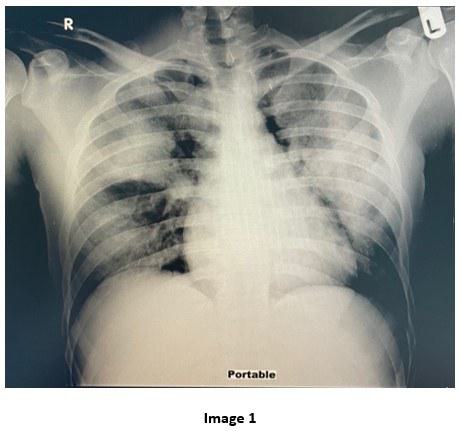

A 28-year-old male with Hepatitis C and history of substance abuse including synthetic marijuana and crack cocaine who presented with acute onset shortness of breath, hemoptysis and chest tightness of 2 hours duration. Upon evaluation, he was found to be hypoxic with SpO2= 80% on non-rebreather mask (FiO2= 100, Flow= 15L/min) requiring intubation. Complete Blood Count (CBC) revealed leukocytosis WBC= 21.13 x10 3 with neutrophilic predominance (92%) and left shifting of +1. Renal panel without major electrolyte disturbance or acid base disorders. The urine toxicology positive for Cocaine and THC. Mycoplasma IgM titers, Influenza A and B titers and Mycobacterium tuberculosis smear and culture were all negative. He was treated with systemic corticosteroid, scheduled bronchodilators and started on broad spectrum antibiotics. He was admitted to the Medical Intensive Care Unit. The chest X-ray and chest CT obtained are shown below